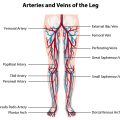

Il nostro sistema capillare periferico ha la capacità di drenare i liquidi in eccesso nei tessuti trasferendoli nel circolo linfatico che, a sua volta, riverserà tali liquidi “sporchi” nel circolo venoso di ritorno al cuore.

Nel caso in cui il circolo linfatico risulti alterato o in presenza di condizioni patologiche concomitanti che favoriscano l’accumulo abnorme di liquidi, le capacità di drenaggio del sistema capillare verranno sovrastate ed i liquidi in eccesso si accumuleranno nei tessuti dando luogo all’edema periferico.

Ad esempio gli edemi da insufficienza venosa degli arti inferiori avranno localizzazione monolaterale o bilaterale asimmetrica, saranno più declivi colpendo prevalentemente piedi e caviglie, peggioreranno durante la giornata con l’ortostatismo migliorando invece con il riposo e durante la notte, si accompagneranno spesso alla presenza di vene varicose o discromie cutanee.

Gli edemi da insufficienza linfatica invece si localizzeranno a tutto l’arto e saranno bilaterali nel caso del linfedema primario (congenito) e monolaterali in caso di linfedema secondario (ad esempio dopo traumi o infezioni).